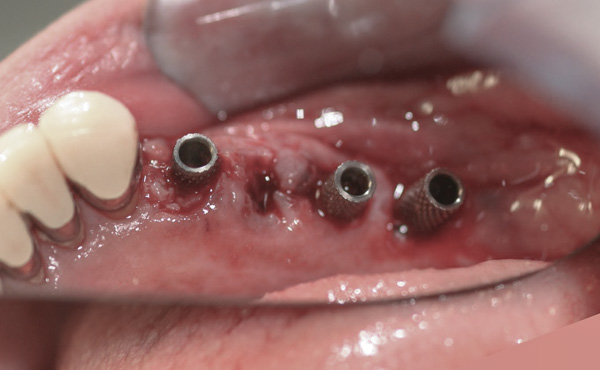

Results: The decision was made to remove these abutments and make a fixture-level impression of all the implants so that both new and first-stage abutments could be milled together for parallelism and proper gingival margin location. Because this requires the removal of the first-stage abutments that were retaining the provisional prosthesis, temporary abutments were placed prior to removal of all custom abutments in order to assure proper seating and vertical dimension of the provisional. These temporary abutments then retained the provisional while all custom abutments were fabricated and/or milled in the laboratory. Figure 12 shows the placement of the remilled (first-stage implants) and new (second-stage implants) custom abutments.

Figure 12 Remilled and new custom abutments.

Figure 12